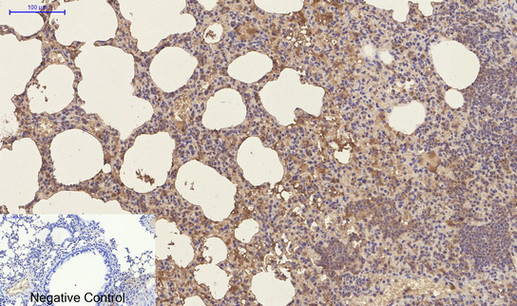

Product Image |

| IHC | 1/50-1/100 |

| ICC | 1/50-1/200 |

Mouse Monoclonal Antibody to CD23

| This receptor has essential roles in the regulation of IgE production and in the differentiation of B-cells (it is a B-cell-specific antigen). | |

| Species Reactivity | Human,Mouse,Rat |